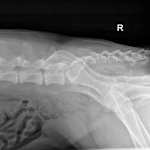

- Radiographs

- Radiographs are normal

- MRI normal–ruled out a tumor, fracture, or infarct

- Diagnosis of DM through elimination–using PE findings and supportive genetic test results